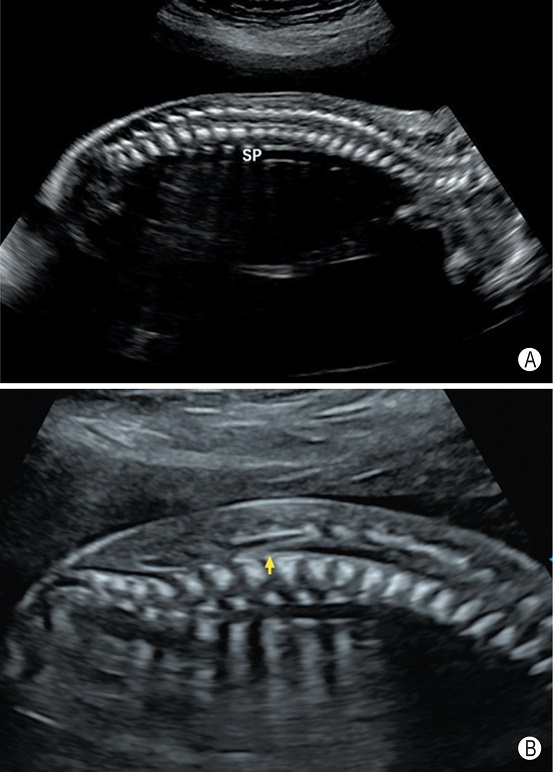

3.脊柱矢状切面

切面要求:显示脊柱全长及其表面覆盖的皮肤(图3),可以分段留存图像。

观察内容:脊柱呈自然生理弯曲,表面皮肤覆盖,椎体及椎弓排列整齐。

图3 孕23周脊柱矢状切面 A和B分别显示脊柱及其表面覆盖的皮肤(SP:脊柱;箭头所示为脊髓圆锥)